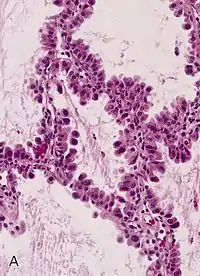

Corte histológico

Una sección histológica o corte histológico es una sección o rodaja fina de un tejido biológico adherida sobre un portaobjetos y generalmente coloreada con alguna tinción específica para resaltar una parte de la estructura.[1] Por lo general, se cortan con un micrótomo con un espesor de unos 0,5 a 10 micras, aunque lo más común es que sean de 3 a 6 micras, porque deben ser atravesados por la luz para que puedan ser observados bajo un microscopio.[2] Se emplean con frecuencia en los laboratorios de histología y de anatomía patológica.

Tinción y montaje

El método de tinción de rutina es el denominado como Hematoxilina - Eosina (H-E). La hematoxilina es un colorante nuclear, y la Eosina, citoplasmático. También existen las denominadas técnicas especiales, tal como: Gomori (para fibras de reticulina), Ziehl neelsen (para bacilos ácido-alcohol resistentes), Grocott (para hongos), Orceína (para fibras elásticas), Gordon-Sweet, Red Sudán, black Sudán, azul de Nilo, Golgi, etc.

Además de las técnicas especiales, se realizan a pedido del patólogo diversas técnicas de inmunohistoquímica como Vimentina, H45, Desmina.

Técnica de Hematoxilina-Eosina:[4]